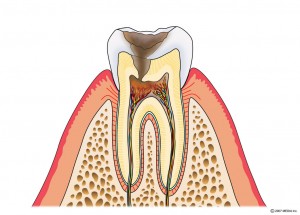

左から

歯肉炎:歯周病の一歩手前の状態で歯ぐきに炎症が起きている状態で

す。

軽度歯周炎:歯周炎ポケットが4~5mmの状態です。

中度歯周炎:歯周ポケットが6~7mmの状態です。

重度歯周炎:歯周ポケットが7mm以上の状態です。